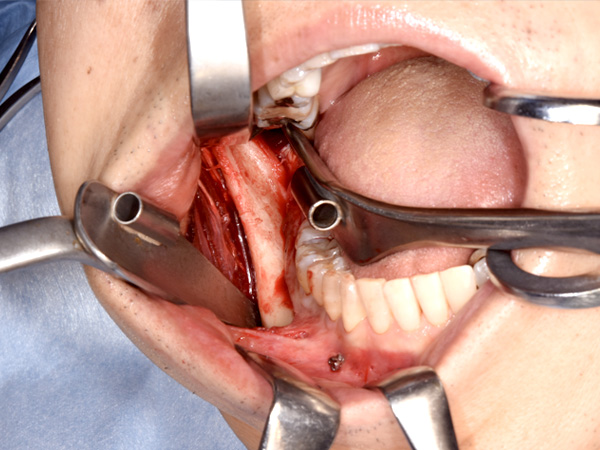

切開して、骨を露出します。

舌側の神経に気を付けながら、骨を切り始めます。

骨が切れて、分離しました。

干渉部分を鏡で確認して切除します。

ぶつかっていた骨を取り除きます。